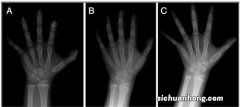

- 我来告诉你骨龄是什么?怎么知道孩子的骨龄